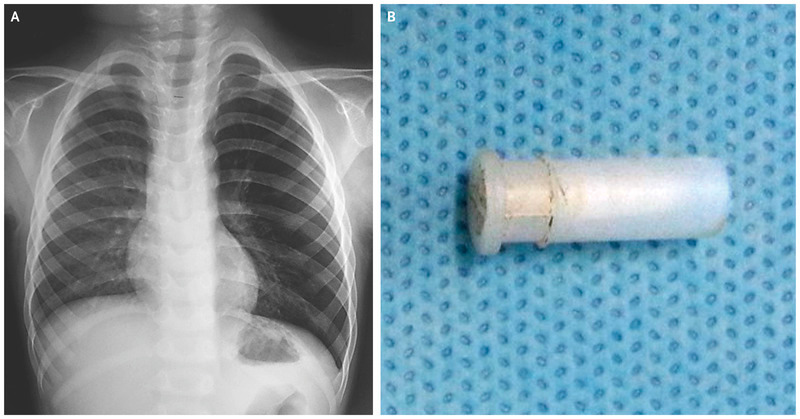

Image Source : England Journal Medicine

When doctors took an X-ray of his chest, they found his left lung to be has some object blocking the air passage. His parents reported that the kid had been playing with a whistle before the cough began.

That's when doctors decided to perform bronchoscopy which is a procedure that involves inserting a thin tube down through the throat and into the lungs.